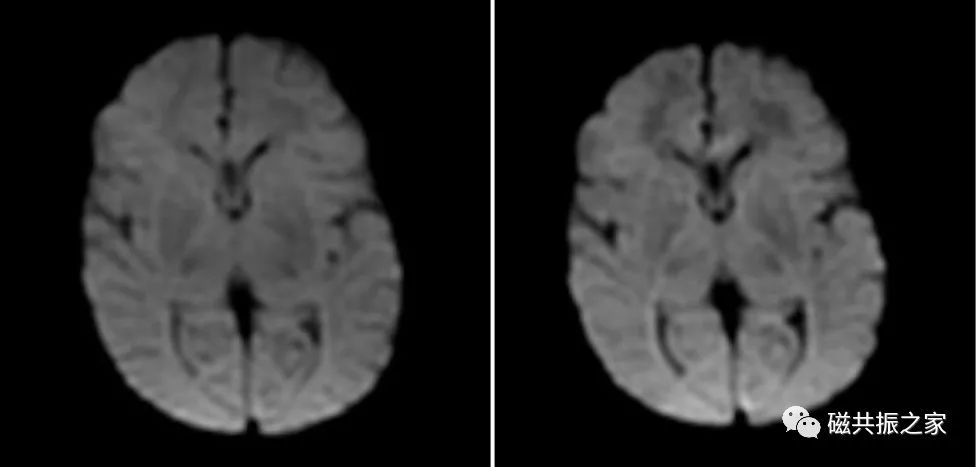

患儿4d,左:B=700;右:B=1000。为了保证图像质量,控制SAR值等问题,对于新生儿颅脑扩散加权成像的B值不宜过大,相关文献建议采用B=700扫描。